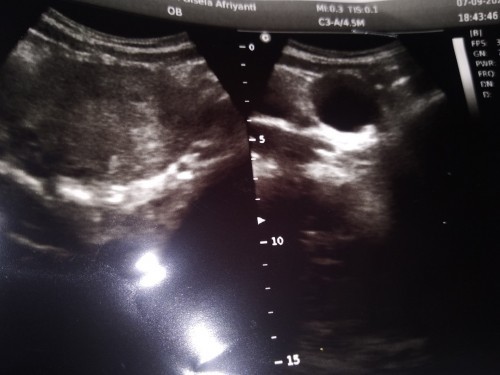

Bun wajar ga si kehamilan jalan 7 minggu baru keliatan kantong janin nya saja makasi

memang kalo 7 minggu keatas baru keliatan kantongnya aja mom, nanti kalo udh tm2 baru keliatan ada isinya

aku usg 10w ud ad janin dan djj bund